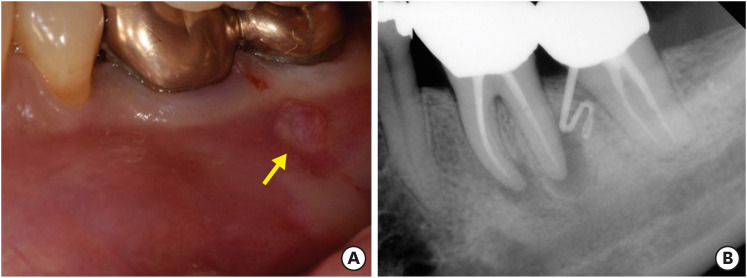

No postoperative complications were reported and the healing process was uneventful. The sutures were removed 7 days after the surgery. The patient presented for follow-up at 6 (Figure 4A and 4B) and 12 (Figure 4C) months with radiographic signs of healing and no clinical signs or symptoms.

Figure 4

(A) The 6 months follow-up clinical image. (B) The 6 months follow-up periapical radiograph. (C) The 12 months follow-up periapical radiograph.

Figure 4 (A) The 6 months follow-up clinical image. (B) The 6 months follow-up periapical radiograph. (C) The 12 months follow-up periapical radiograph.